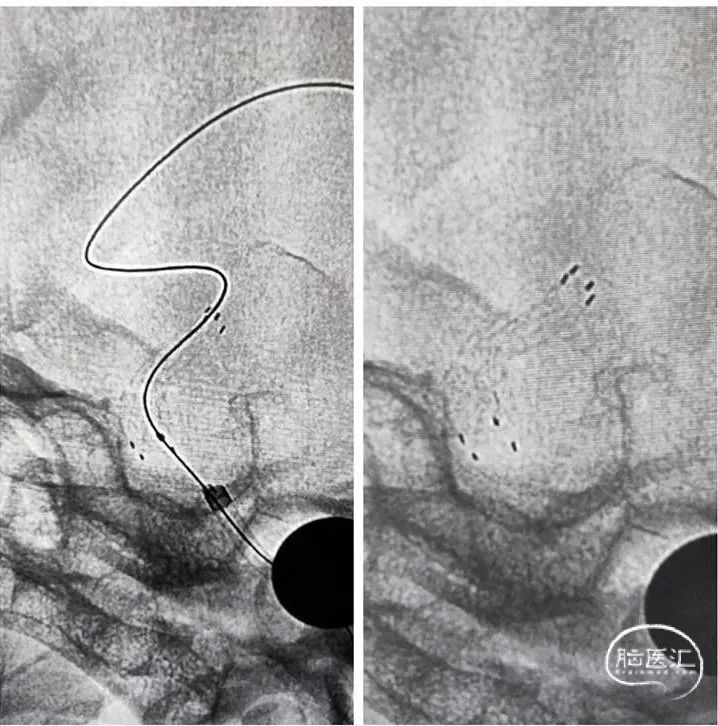

栓塞前

栓塞后

栓塞前

栓塞后

半年后复查造影支架内再狭窄。

2

加奇SacSpeed®2.0×15mm球囊预扩张后2×10mm药涂球囊扩张。

3

狭窄明显改善。